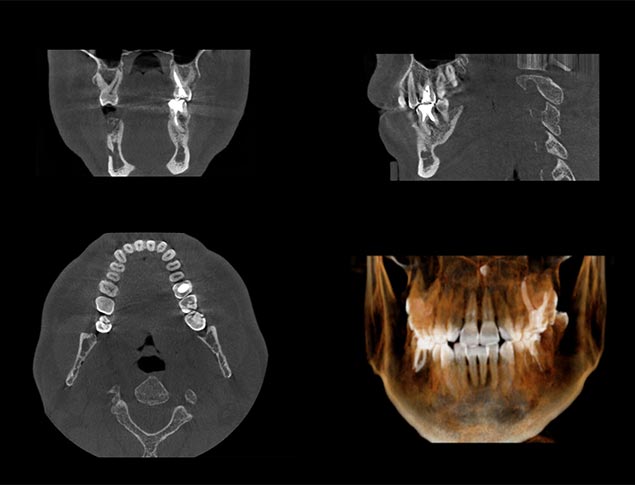

A cone beam CT scan involves a special type of x-ray that allows us to see the details of your oral and facial health. This scan is more than just a typical x-ray, since it allows us to identify nerve pathways, soft tissue and bone before providing you with treatment. This gives us a clear view of your oral health so that treatment is easier and more effective for you. The scan takes just seconds in our office and provides us with a highly detailed image.

The process will begin by placing a lead apron over your body before the scan is done. We then have you stand straight in the middle of a larger machine. You will either rest your chin or bite down on a bite bar. The machine will then circle your head, taking images as it turns around. We are provided with this image after just a few seconds and will review it to provide you with the treatment that you need. You can expect to have a CT scan prior to undergoing oral surgery.